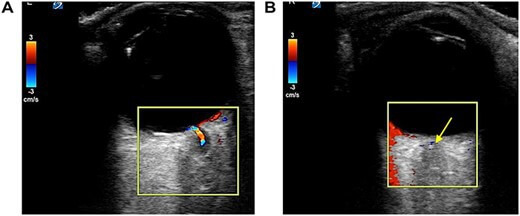

Zur weiteren Beurteilung des Auges führen die Ärzte einen Ultraschall unter Verwendung einer Hochfrequenz-Linearsonde durch. Dabei zeigt sich ein retrobulbärer Fleck im distalen Abschnitt der zentralen Netzhautarterie.

Während das linke Auge normal durchblutet scheint, ist in der zentralen Netzhautarterie des rechten Auges kein Blutfluss messbar.